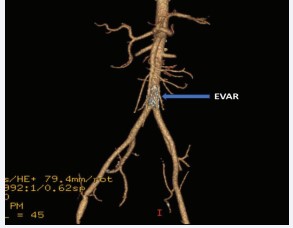

His hospital course after the laparotomy was largely uneventful. His L3 burst fracture was treated conservatively by neurosurgery with a lumbar-sacral orthosis brace. He had advancement of diet and activity then discharged home on the 8th postoperative day. Prior to discharge, a follow-up CT angiogram was performed to assess the aortic repair which demonstrated complete exclusion of the area of injury with the endovascular stent graft with widely patent IMA and iliofemoral run-off vessels [Figure 3].

Figure 3: Follow-up computed tomographic angiography, maximum intensity 3-D projection obtained prior to hospital discharge demonstrating complete exclusion of the area of injury with the endovascular stent graft (EVAR), as well as widely patent iliofemoral run-off vessels.